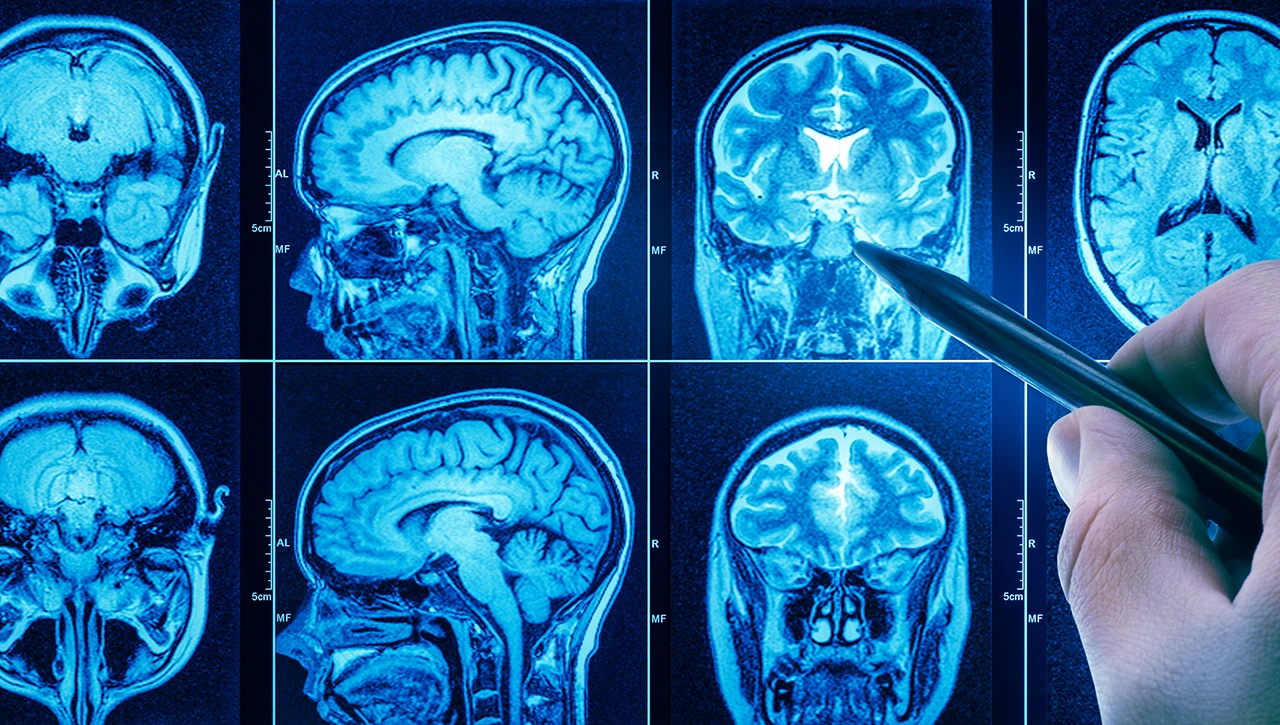

Pruebas de imagen avanzada

El primer paso suele ser una Resonancia Magnética (RM) con contraste, que permite visualizar la masa encefálica con gran detalle. En algunos casos, se utiliza la Tomografía Computarizada (TC) para evaluar posibles afectaciones óseas o hemorragias agudas. Estas imágenes son fundamentales para que el neurocirujano planifique cualquier intervención futura.